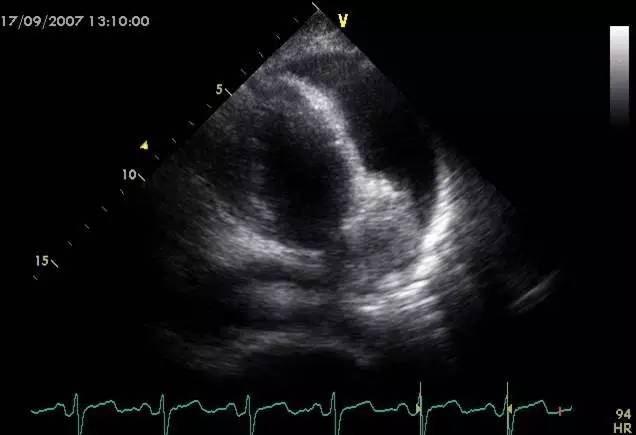

l超声心动图是一线检查

l经胸超声心动图

cardiac tamponade and pulsus paradoxus